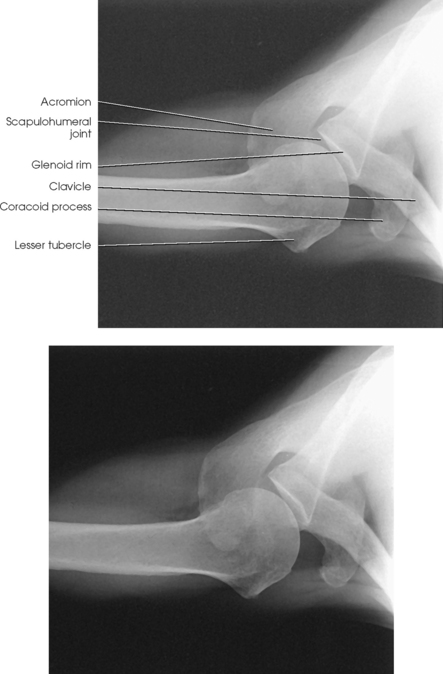

Structures shown: The image shows the bony and soft structures of the shoulder and proximal humerus in the anatomic position (Figs. 5-14 to 5-16). The scapulohumeral joint relationship is seen.

Fig. 5-14 A, AP shoulder, external rotation humerus: greater tubercle in profile (arrow). B, AP shoulder, neutral rotation humerus: greater tubercle (arrow).

Fig. 5-15 AP shoulder, internal rotation humerus: greater tubercle (arrow); lesser tubercle in profile (arrowhead).

External rotation: The greater tubercle of the humerus and the site of insertion of the supraspinatus tendon are visualized (see Fig. 5-14, A).

Neutral rotation: The posterior part of the supraspinatus insertion, which sometimes profiles small calcific deposits not otherwise visualized (see Fig. 5-14, B), is seen.

Internal rotation: The proximal humerus is seen in a true lateral position. When the arm can be abducted enough to clear the lesser tubercle of the head of the scapula, a profile image of the site of the insertion of the subscapular tendon is seen (see Fig. 5-15).